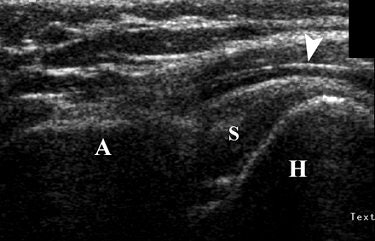

During this active exam, the relationship between the acromion, humeral head, and soft tissues were assessed. If the humeral head passed easily underneath the acromion during shoulder movement, then impingement was ruled out, the authors stated. Otherwise, readers looked for soft-tissue or osseous impingement.

| Forty-three-year-old man with upward migration of humeral head during dynamic sonography evaluation of shoulder. Coronal sonography view of left shoulder with shoulder impingement syndrome, during active elevation of arm halfway between flexion and abduction with hand in pronation, shows abnormal upward migration of humeral head (H) in regard to acromion (A), preventing its passage underneath acromion. There is mild distension of subacromial bursa (arrowhead). S = supraspinatus tendon. Bureau NJ, Beauchamp M, Cardinal E, Brassard P, "Dynamic Sonography Evaluation of Shoulder Impingement Syndrome" (AJR 2006; 187:216-220). |

According to the results, there were 14 shoulders with subacromial impingement. In this group, 14% were diagnosed on dynamic sonography and 50% of those were given a grade 3. In the 12 asymptomatic shoulders, 75% were given a grade 0.

"In grade 3 subacromial impingement, there is a failure of the humeral depression resulting in upward migration of the humeral head," Bureau's group stated, adding that possible causes include shoulder joint instability or rotator cuff muscle fatigue.